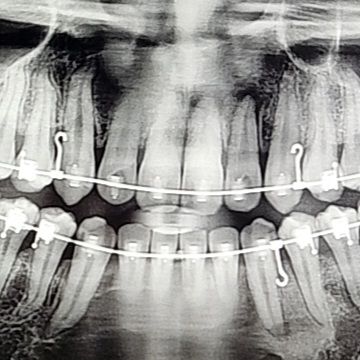

갑자기 금일 진료 간 일반과에서 x-ray 판독 시 치아 뿌리에 염증이 있는 것으로 보인다고,, 치료가 필요하다고 합니다. 자연치유의 가능성은 없는 것인지 신경치료가 시급한지

안녕하세요. 정경호 치과의사입니다. 올려주신 방사선사진의 quality로는 정확한 진단은 불가하며, 교정 중에는 치아 이동 과정에서 전반적으로 치아뿌리 부분에 간혹 다소 방사선투과성(검은색)의 부분이 보이는 경우가 있습니다. 다만, 한 치아에만 국한되어 명확한 치아뿌리 염증 소견이 있다면, 치과에서 치수생활력 검사를 받아보시는 것이 좋겠습니다.

사진상으로 오른쪽 가운데서 두번쨰 치아 뿌리끝에 염증이 잇어 보입니다. 증상이 잇다면 신경치료를 해야될수도 잇을것같습니다.